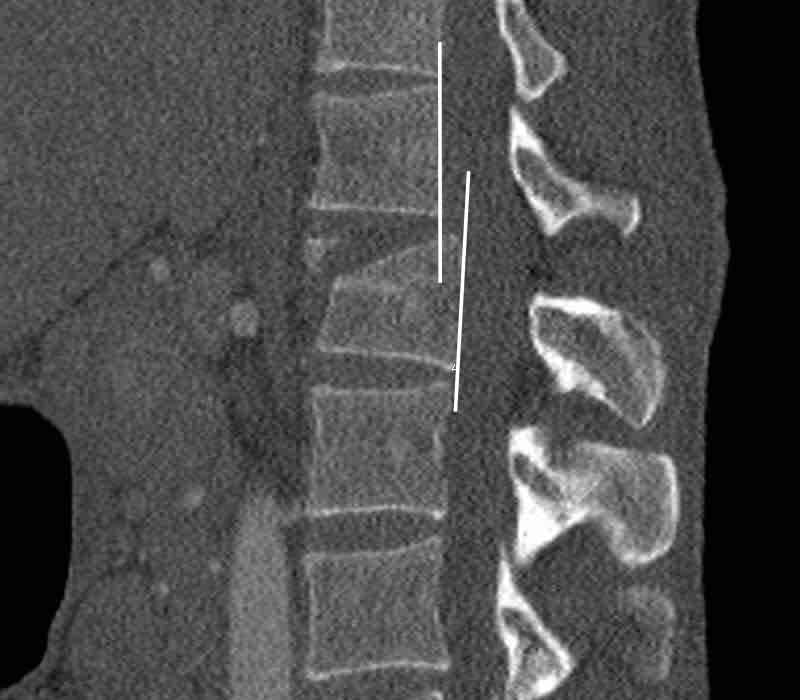

Scroll through the images.

What are the findings?

What is the highest AO-type of injury?

Findings

- Vertical fracture of the posterior border of the vertebral body. It looks a bit odd.

- Again we first have to look for the presence of a type C injury.

- Notice that there is a subtle posterior dislocation of the proximal levels. So this has to be C injury.

Conclusion

Injury type C + A3